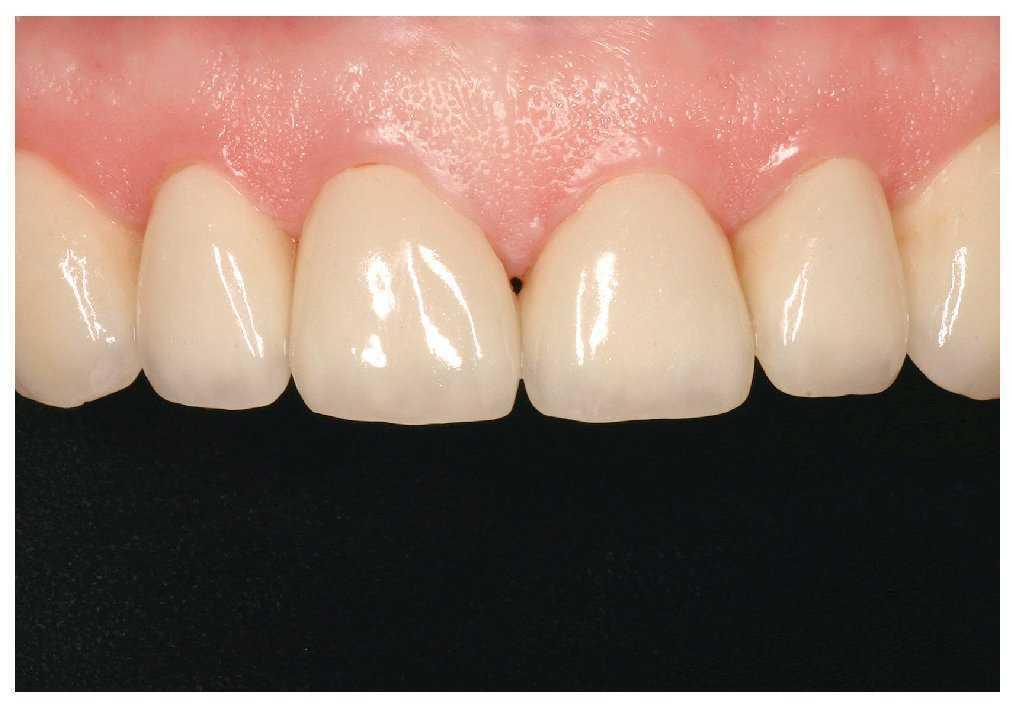

La primera revisión se realizó a los tres días de la colocación (figs. 23 y 24) y las siguientes tuvieron lugar al cabo de una, dos y cuatro semanas. Se estableció una frecuencia trimestral de las visitas de revisión. Además de controlar la oclusión, la función y la férula inferior se realizaron reevaluaciones periódicas de la situación periodontal. Con la adopción de otras medidas de tratamiento periodontal inicial a los tres y a los nueve meses en el maxilar y en la mandíbula fue posible disminuir de forma duradera las profundidades de sondaje.

Figura 23. Aspecto de las restauraciones anteriores durante la primera revisión.